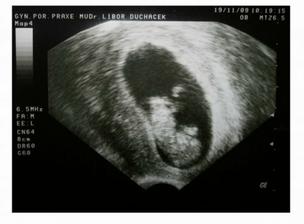

V 11tt vystavena těhotenská průkazka.

Následně provedeny testy na vrozené vady - vše dopadlo dobře.

Ve 20tt velký utrazvuk - také vše v pořádku.